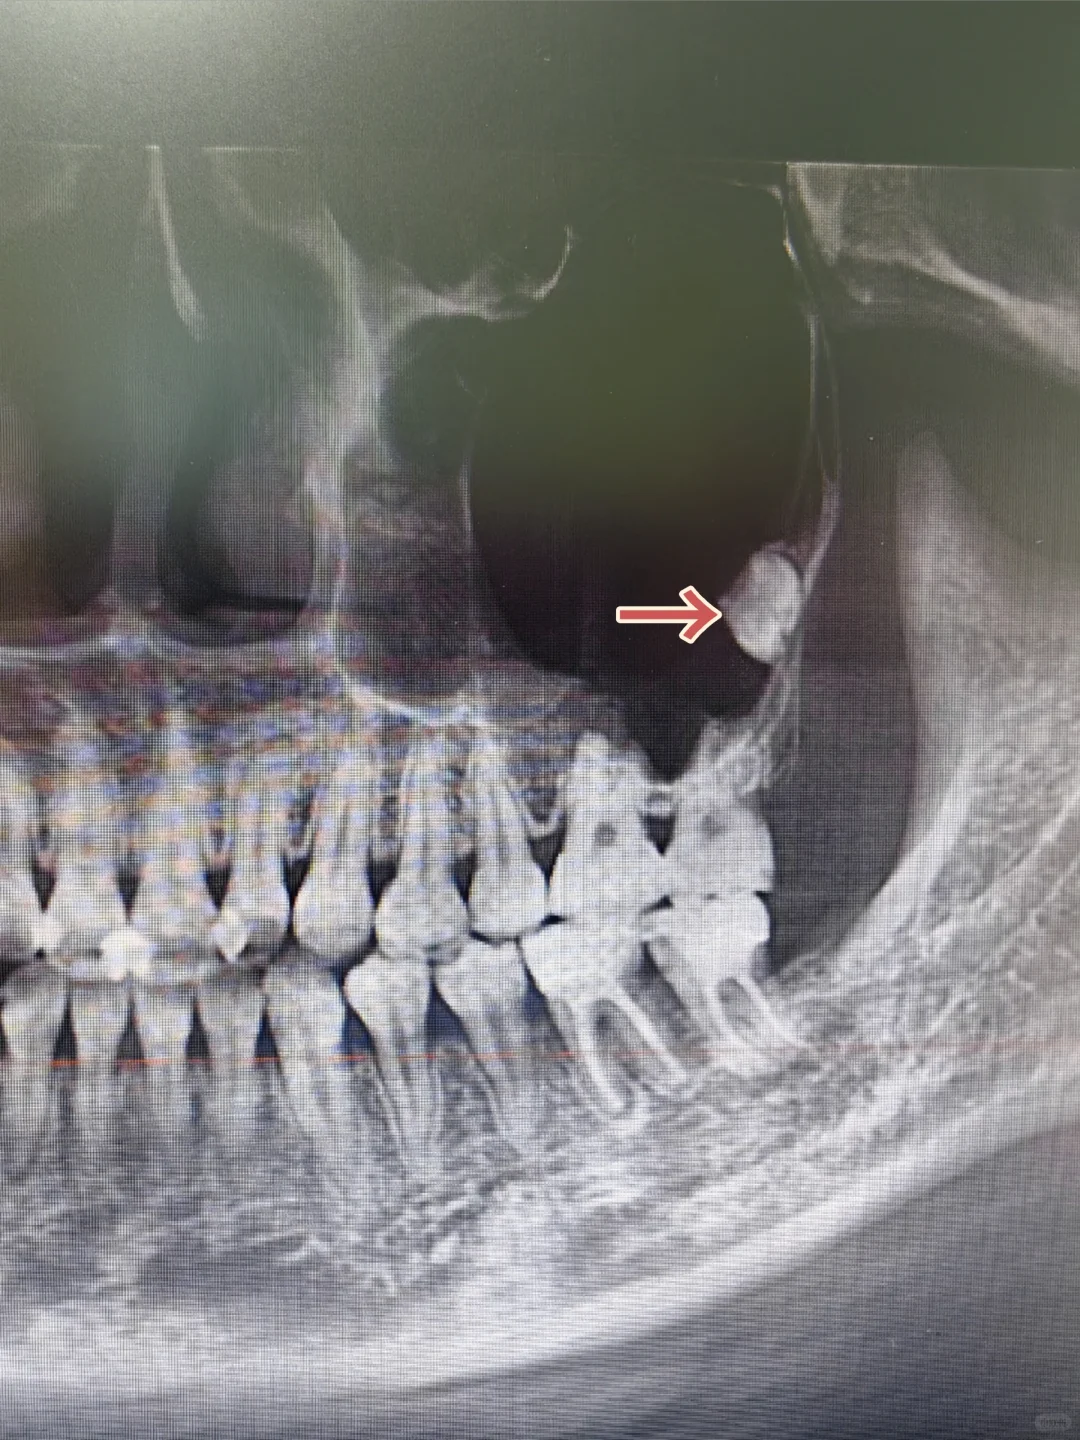

[哇R]图一去右下颌骨内含牙囊肿,牙齿倒置长再骨头里面~ [哇R]图二去左下第二磨牙埋伏,智齿又压在磨牙上面,一起阻生在骨头里面~ [失望R]锤哥一天能遇到这两位卧龙凤雏,也是我职业生涯中浓墨重彩的一笔啊